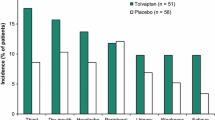

Arginine-vasopressin (AVP or antidiuretic hormone, ADH) type 2 receptors (V2-R) are expressed in the kidney collecting ducts (CDs). By acting on these receptors, AVP increases cAMP production, leading to the insertion of aquaporin-2 (AQP-2) into the apical membrane of CD, allowing water reabsorption and decreasing urine output (Fig. 1)6. In SIAD, plasma AVP levels are inappropriately increased with respect to plasma osmolality1. V2-R antagonists, such as tolvaptan, block the stimulation of V2-R by AVP, and have been shown to correct hyponatremia efficiently in rodents7 as well as in humans with SIAD8,9,10. Expected effects of aquaretic agents such as intense thirst, polyuria (24 h diuresis up to 6 L per day) and nocturia were observed11. Tolvaptan at the dose of 7.5 mg per day was also reported to carry a significant risk of overly rapid sodium correction in 23% of hyponatremia patients having baseline serum sodium concentration <125 mmol/l12. These patients exhibit the highest risk of developing osmotic demyelination syndrome when overly rapid correction of hyponatremia occurs13,14. Chronic treatment with V2-R antagonists has also shown efficacy in autosomal dominant polycystic kidney disease (ADPKD)15. However, aquaresis-related events led 8% of patients with ADPKD receiving tolvaptan to discontinue treatment15,16,17. Therefore, the development of therapeutic agents acting on different targets with a different mode of action could be useful for the treatment of disorders linked to excessive AVP secretion such hyponatremia and ADPKD.